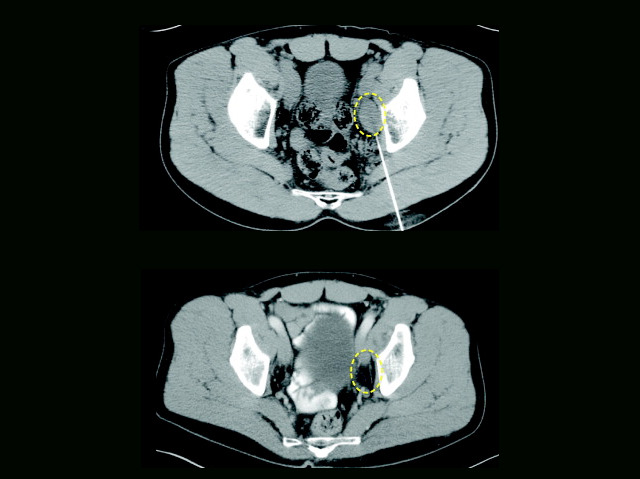

T cells – members of our body’s defence team – roam around detecting and killing infected or damaged cells. To make certain they don’t harm healthy tissue, they only inject their deadly poisons once there is a perfect match between their unique receptor [a protein on their surface] and markers on ‘corrupted’ cells. Cancer evades attack because it looks very similar to normal cells. So researchers have taken a patient’s T cells, genetically-modified their receptor so it can react with cancer and then returned them. This is a horizontal scan through the belly of a patient with advanced cancer (pelvic bones, and backbone at the bottom of scan in white). The cancer (circled in yellow) seen before T cell treatment (top) cannot be detected two years later (bottom). Although good news, it doesn’t work every time so researchers are working on how to optimise the T cell receptor for each patient.